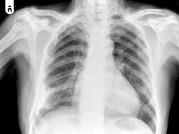

问题 男,77岁,全身性骨痛,夜间加重,贫血,PSA大于100,结合图像,最可能的诊断是?(?)

选项 A.成骨性骨转移 B.多发性骨髓瘤 C.慢性化脓性骨髓炎 D.骨肉瘤 E.以上都不是

答案 A